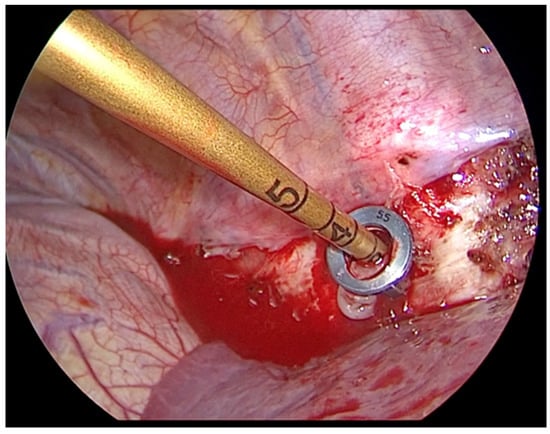

- The risk of bleeding is possible especially near the Azygos vein. The vascular dissection must be delicate and precise, using a bipolar forceps or a thin instrument combined with a bipolar coagulation device. The parietal pleura must be incised carefully along the marginal spine and a good exposure of the veins must be achieved. Small branches of the paravertebral veins need accurate hemostasis.

- A correct interaction between pediatric and orthopedic surgeon, integrated by the combined use of thoracoscopic visualization and fluoroscopy, allow the orthopedist to correctly position the devices at the level of the vertebrae to be treated.